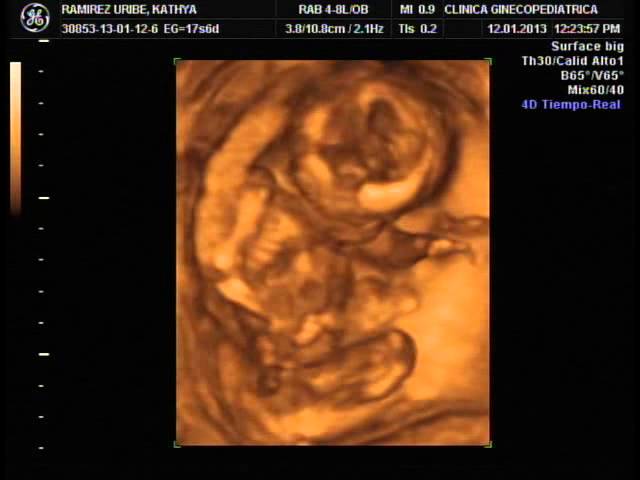

Ecografia 4d embarazo de 13 semanas 4d dr. Ya estas de 13 semanas de embarazo. En la ecografia 4d se aprecian perfectamente todas sus estructuras basicas cabeza tronco extremidades incluso los genitales masculinosdestaca la bipedestacion de la figura se encuentra erguida que parece mas humana de lo que podriamos imaginar a esa edad gestacional. Es que yo segui con el periodo si no por cambios en mi cuerpo realice la prueba me salio positiva y cuando fui al medico por sangrado me dijieron que tenia 13 semanas ja.

Rafael ortega munoz en la cual se muestra un feto de 13 semanas en 4d moviendose download me its free. La resonancia magnetica rm es un examen medico no invasivo que ayuda a diagnosticaralgunas enfermedades. Ecografia 4d 3d dr. El bebe presenta el reflejo prensil y el de sobresalto.

Para que te hagas una idea es mas o menos como un lapiz. Ecografia 4d 3d 2d realizada en la unidad de ecografia de la clinica ginecologica del dr.

Con esta ecografia es posible diferenciar a las pocas semanas de gestacion 12 o 13 semanas de embarazo todas las partes del rostro del feto como nariz boca ojos orejas y otras como el craneo el cerebro y muy importante el corazon. En semanas posteriores a la 25 vereis al bebe por partes pues estara demasiado grande por ello cuando se hace una ecografia 3d o 4d en esta fase del embarazo se enfoca sobre todo a la carita para ver los rasgos y sus gestos. Puede solicitar su resonancia magnetica en utm. Tu ginecologo y matrona ya te habran dicho que el mito de que las embarazadas deben comer por dos es falso.